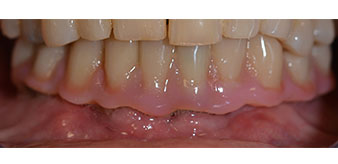

Im Anschluss erfolgt die Abformung und Bissnahme, sodass die Zahntechniker umgehend mit der Anfertigung der provisorischen Arbeit beginnen können. Diese wird im Anschluss am gleichen Tag eingeschraubt (Abb. 17 und 18).

Implantate

Abb. 17

Abb. 18